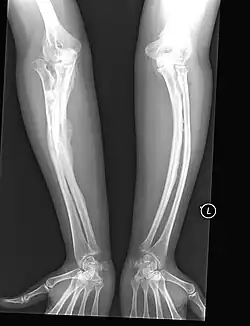

Typ-V-OI bei einem Erwachsenen; Röntgenbild der Arme

Betroffene dieses Typs neigen zum seltenen Phänomen des sogenannten hyperplastischen Kallus (Callus luxurians), einer spontan überschießenden Kallusbildung ohne eine hierfür übliche Fraktur mit anschließender Verknöcherung. Durch Einlagerung von Calciumsalzen in die bindegewebigen Strukturen (Syndesmosen) zwischen den beiden Unterarmknochen Elle und Speiche sowie den Unterschenkelknochen Schien- und Wadenbein (Calcifizierung der Membranae interosseae antebrachii et cruris) ist die Ein- und Auswärtsdrehung (Pronation/Supination) des Unterarms bzw. des Unterschenkels der Betroffenen erheblich blockiert, was zur klinischen Differentialdiagnose hilfreich ist, sofern die Bewegungseinschränkungen nicht auf Deformierungen der entsprechenden Knochen oder Gelenke beruhen.